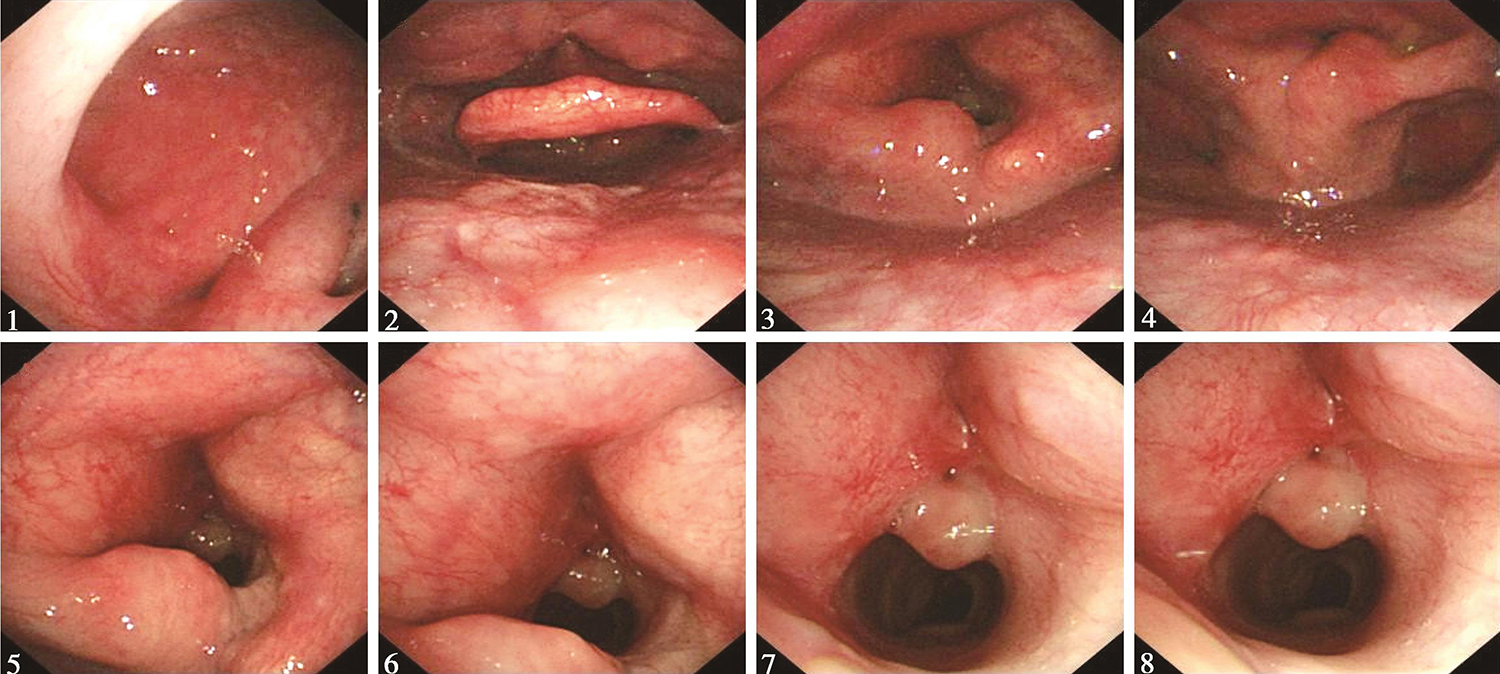

1.2015年9月22日电子鼻咽喉镜检查

“喉癌术后3个月”,鼻腔进镜顺利。鼻咽部结构完整,黏膜光滑,未见明显异常。口咽双侧扁桃体未见肿大。舌根部淋巴滤泡增生明显。下咽部表面光滑,未见明显异常。喉部会厌及双侧披裂结构完整,声门区呈术后改变,双侧声带基本切除,原前联合位置可见肉芽结节(图3)。声门裂开放尚好。左右半喉活动未见明显受限。

图3 2015年9月22日复查喉镜示双侧声带基本切除,原前联合位置见肉芽结节

内镜诊断:

喉癌术后,声门区呈术后改变,双侧声带基本切除,声门区可见肉芽结节,未见肿瘤征象。

3.2016年2月22日电子鼻咽喉镜

“喉癌术后半年余”,鼻腔进镜顺利。鼻咽部结构完整,黏膜光滑,未见明显异常。口咽双侧扁桃体未见肿大。舌根部淋巴滤泡增生明显。下咽部表面基本平整,未见明显异常。喉部声门上结构基本完整,双侧披裂保留,黏膜充血。声门区左侧声带切除,声门区肉芽组织消退,声门区未见明确肿瘤征象(图4)。左半喉基本固定,右半喉活动尚可。

图4 2016年2月22日复查喉镜示声门区肉芽组织消退

喉癌术后,左侧声带切除,残喉黏膜充血,未见明显肿瘤复发征象。